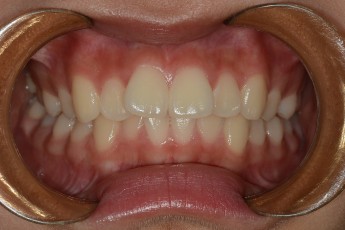

BEFORE & AFTER